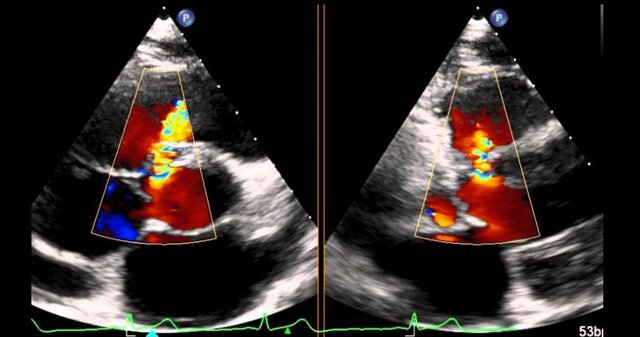

Visualización.

Científicos, ingenieros, personal médico, analistas comerciales y otros necesitan con frecuencia analizar grandes cantidades de información o estudiar el comportamiento de ciertos procesos -